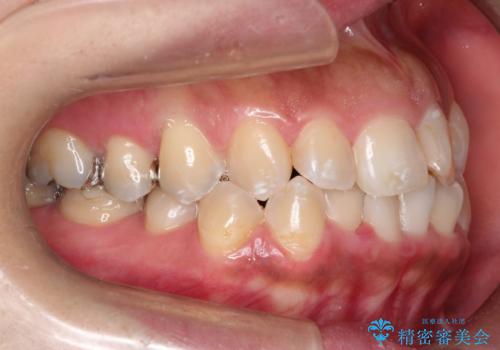

奥歯の噛み合わせは綺麗に噛んでいたため、前歯の叢生(でこぼこ)に集中して治療するように計画しました。

奥歯の噛み合わせは整っていたため、前歯の並びを美しく修正することに専念できました。